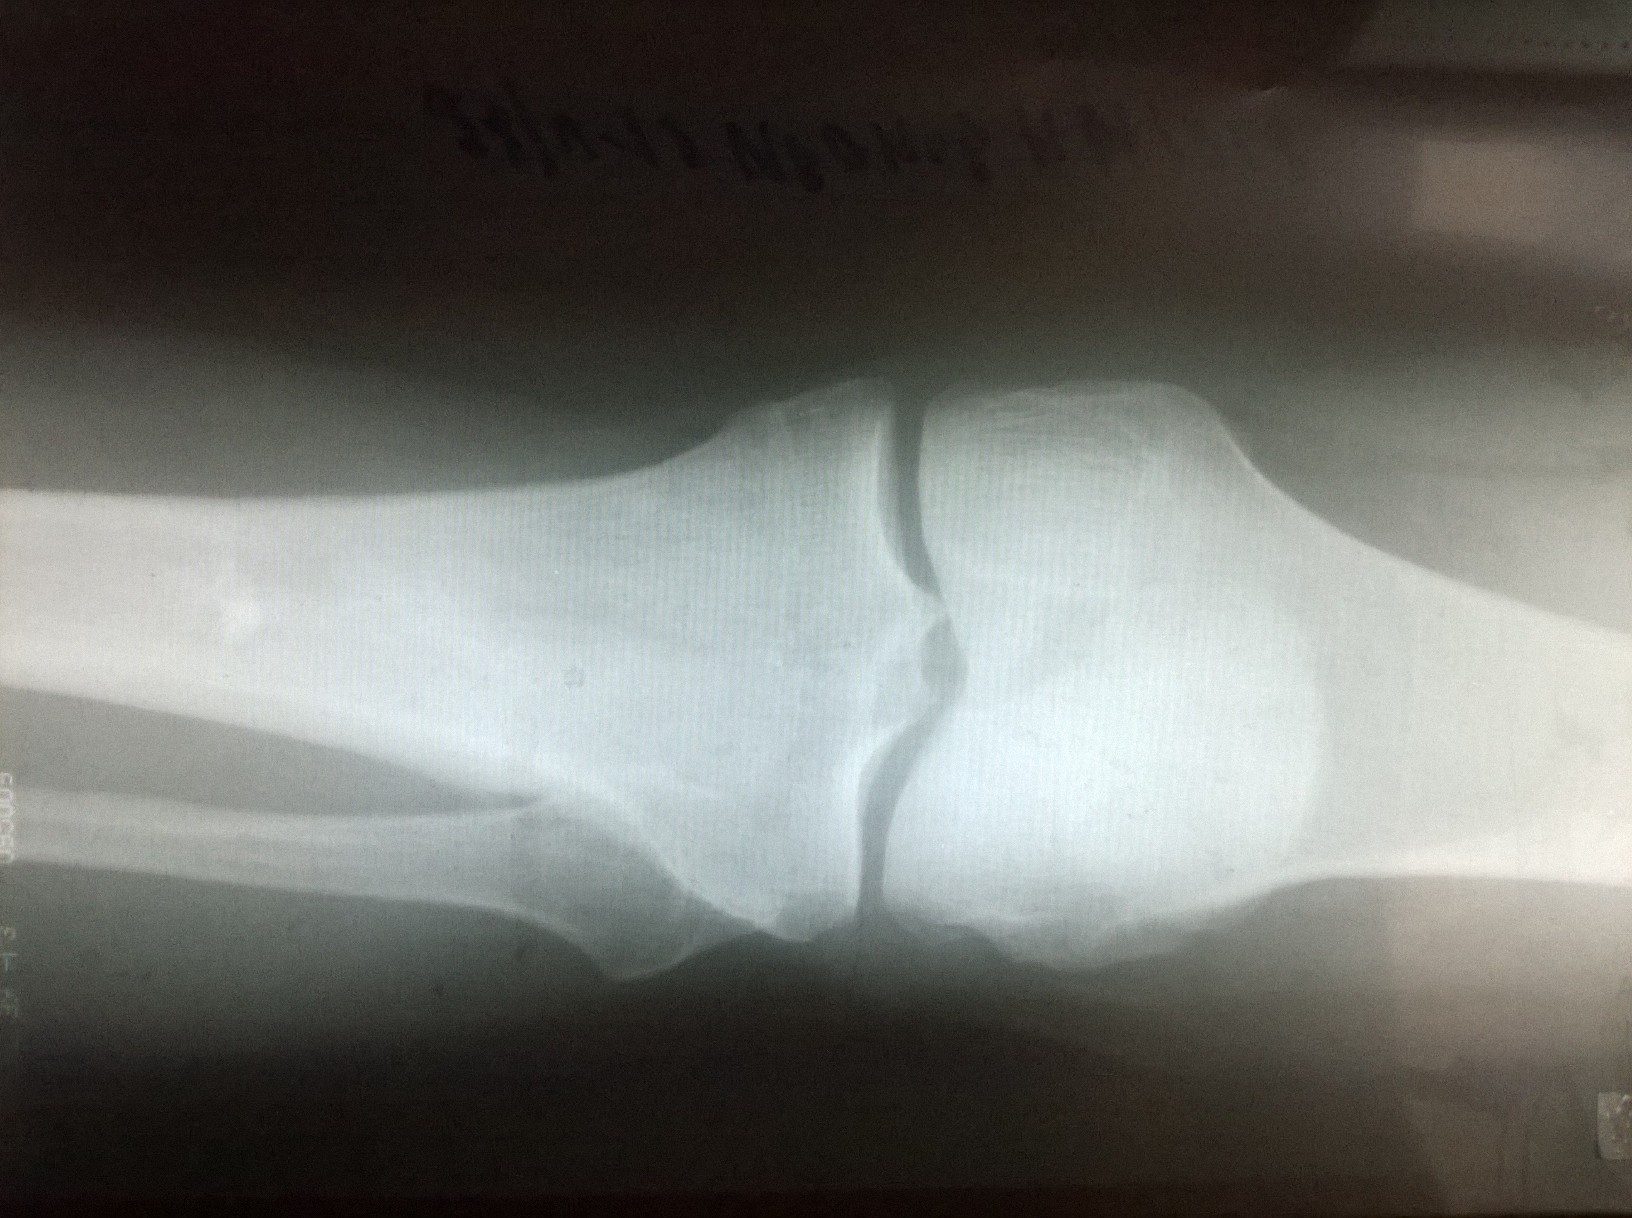

Помогите расшифровать снимок

Участок остеосклероза неправильной формы в верхней трети диафиза б/берцовой кости может быть инфарктом костного мозга.